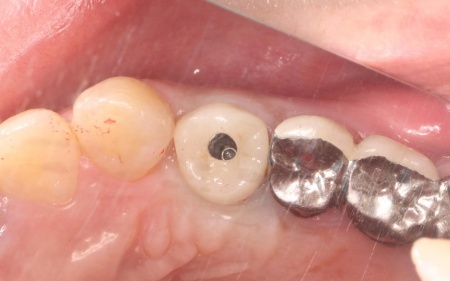

| 行ったご提案・治療内容 | 診断結果をお伝えし、患者様の了承を得たうえで左下奥歯の被せ物を外したところ、レントゲン検査での診断どおり、歯根が割れていることが確認できました。 そのため、患者様には左上下奥歯とも温存が難しい旨を説明し、抜歯に同意いただきました。 患者様は、以前当院で人工歯根を顎の骨に埋入して歯を装着するインプラント治療を受けていたため、今回も左上下奥歯ともインプラント治療を希望されています。 メリット デメリット 改めてメリットとデメリットをしっかりお伝えしたところ、インプラント治療に対する不安はないとのことで、治療に同意いただきました。 まず、左上下奥歯を慎重に抜きます。 インプラント手術後は経過観察を行い、インプラントが顎の骨に結合したことを確認したら、インプラント上部に取り付ける人工歯を作製するために精密な型取りを実施します。 後日、完成した人工歯をインプラントに装着し、使用感や見た目に問題がないことを確認して、治療を終了しました。 |

治療中